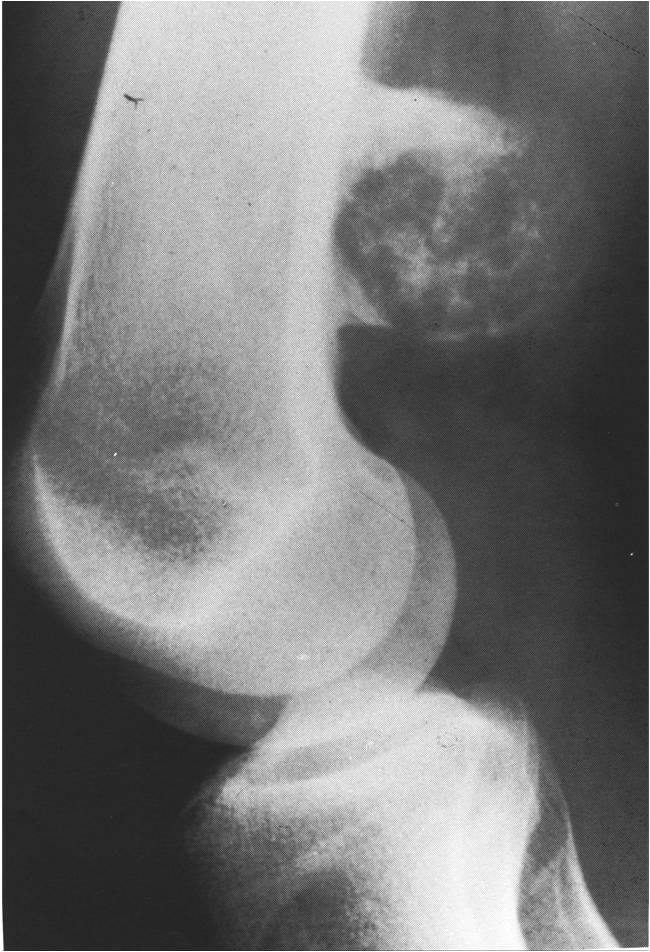

Radiographic Presentation

- Well circumscribed

- Appears to be embedded in underlying cortical bone

- Typically covered by a thin shell of reactive, often ossified periosteum

- Medullary cavity not grossly invaded